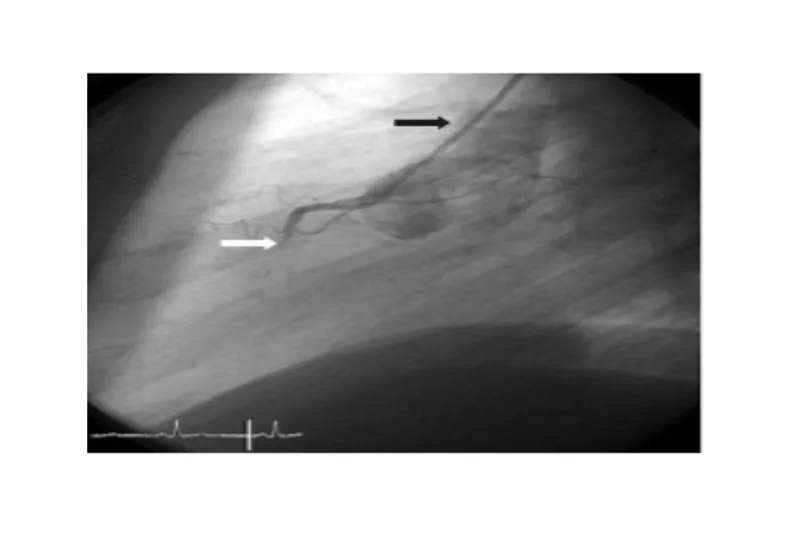

Hjerte-kar-sygdomme deler risikofaktorer med parodontitis, fx rygning og diabetes, og er hyppige lidelser, der ofte kræver kompleks udredning og behandling. Mange patienter klager over anstrengelsesudløst trykken i brystet, åndenød, hjertebanken og/eller hævede ben. De diagnostiske undersøgelser omfatter specielt ekkokardiografi, som belyser hjertets struktur og funktion, arbejds-ekg (cykeltest), hjerte-CT-scanning og koronarangiografi. Patienter med iskæmisk hjertesygdom, hjertesvigt, arytmi eller klapfejl behandles ofte med blodfortyndende medicin, pacemaker eller mekanisk klapprotese, som kræver særlig opmærksomhed ved tandlægebesøg.